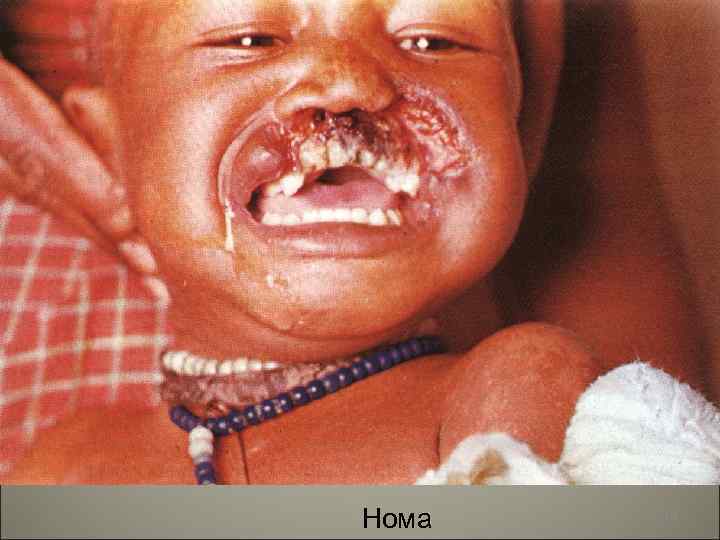

• Осложнения кори- присоединение пневмонии, отиты, мастоидиты. Поражение центральной нервной системы (энцефалит, менингоэнцефалит). Острый некротический ларингит (коревой круп), стоматиты, нома. 108